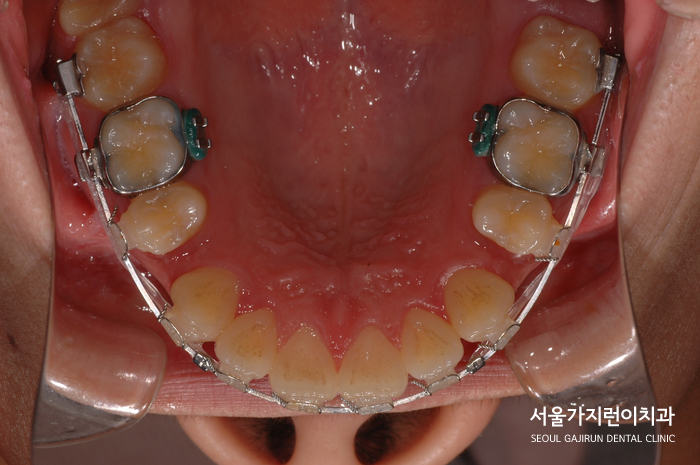

환자분의 경우 초기에는 상악 앞니를 후방으로 밀고 하악은 공간확보를 위해 정렬을 유도했는데요.

교정장치 부착 후 치아이동이 잘 되는 것을 확인했으며 점점 발음과 식사시 불편도 줄었다며 치료도중 만족감도 좋으신 편이었습니다. 게다가 치아가 가지런해지면서 얼굴 윤곽도 부드러워지고 인상이 한층 밝아져 자신감이 생긴 모습이셨는데요.